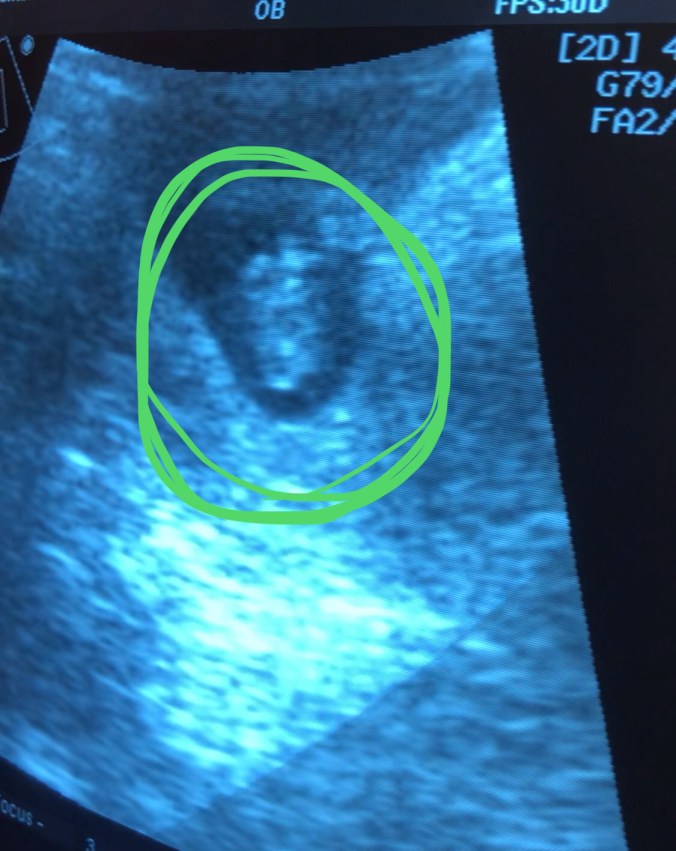

Det skulle gå nesten en uke til før min kone ba meg handle med hjem både poteter og en graviditetstest … Plutselig var jeg tilbake til 2015, spenningen, klokken som teller sekunder … hvorpå det plutselig lyste to streker i mot meg … Stillhet og sjokk … et smil, latter og tårer … Min kone var blitt gravid… Så mange slike tester jeg hadde vært med på, men aldri sett en med to streker på…

Men ukene gikk, og uker ble til måneder, og nå sitter vi her da … ca 15 uker pluss 1 dag, og i neste uke er tid for kontroll hos fastlegen. Jeg vet at det enda er sjanse for at ikke alt går etter planen, men etter at vi gikk forbi uke 12, har jeg klart å finner mer ro, og har evnen til å kjenne på et hav av gode og skumle følelser. Tenk da … VI ER GRAVID ❤ ❤ ❤

VI ER GRAVID, OG DET ER HELT AV OSS SELV

Men svarte svingende !!! Jeg skal bli pappa ❤ 🙂 ❤